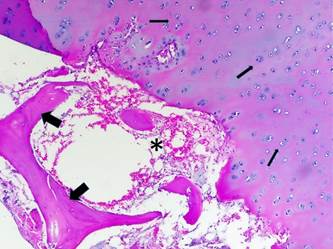

Histopathological diagnosis. The femoral head and neck surgical piece was fixed in 10% formaldehyde and sent for histological-pathological study with haematoxylin and eosin staining in the Histopathology Laboratory of the Universidad Científica del Sur. Histopathologically, a wide variety of trabecular bone necrosis was observed with limited inflammatory changes. The diagnosis corresponded to avascular necrosis of the femoral head and neck (Figures 5 and 6).

Figure 5 Section of necrotic bone, the articular cartilage is thickened and abnormal chondrocyte dispositions are observed (thin arrows). Area of subchondral bone necrosis, there are empty trabecular bone gaps containing necrotic osteocytes (thick arrows). The hematopoietic tissues show depression and you can see atrophic adipose tissue (asterisk) (Hematoxylin and eosin, 20x).

Figure 6 The bone marrow has been replaced by fibrotic marrow in an eosinophilic matrix, this tissue as a whole is partially connected to the necrotic bone (asterisks). Some multinucleated giant cells can be seen in the periphery of the matrix (large arrows). There are some empty gaps in the trabecular bone containing necrotic osteocytes (thin arrows). (Hematoxylin and eosin, 40x).

The histological findings also belonged to the expected findings in a necrotic bone affected by AVNFH 11,14. These changes were reported as empty osteocyte gaps or with necrotic osteocytes. This necrotic bone was surrounded by fibrotic bone marrow, which was disorganized and with abundant collagen fibers. An eosinophilic matrix and some giant multinucleated cells adjacent to the bone trabeculae were also identified in the marrow.